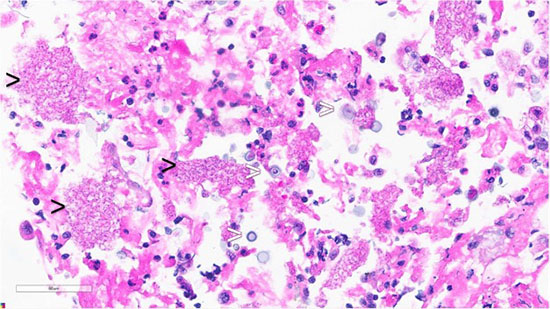

Figure 3: Lung FNA, Cell Block, Hematoxylin and eosin stain: foamy amorphous materials (black arrowheads), Cryptococcus organisms (white arrowheads), with histiocytes and lymphocytes.

Figure 4: Lung FNA, Cell Block, GMS stain: highlights Pneumocystis jirovecii (black arrowheads) and Cryptococcus species (white arrowheads).